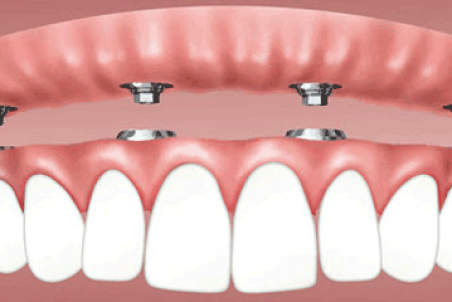

دندان مصنوعی با پایه ایمپلنت و مزایای آن

دندان مصنوعی با پایه ایمپلنت نسبت به دندانهای مصنوعی قدیمی، تاثیر بیشتری در سلامت دهان و دندان افراد دارد و کیفیت زندگی را نیز به طور قابل توجهتری بالا میبرد.